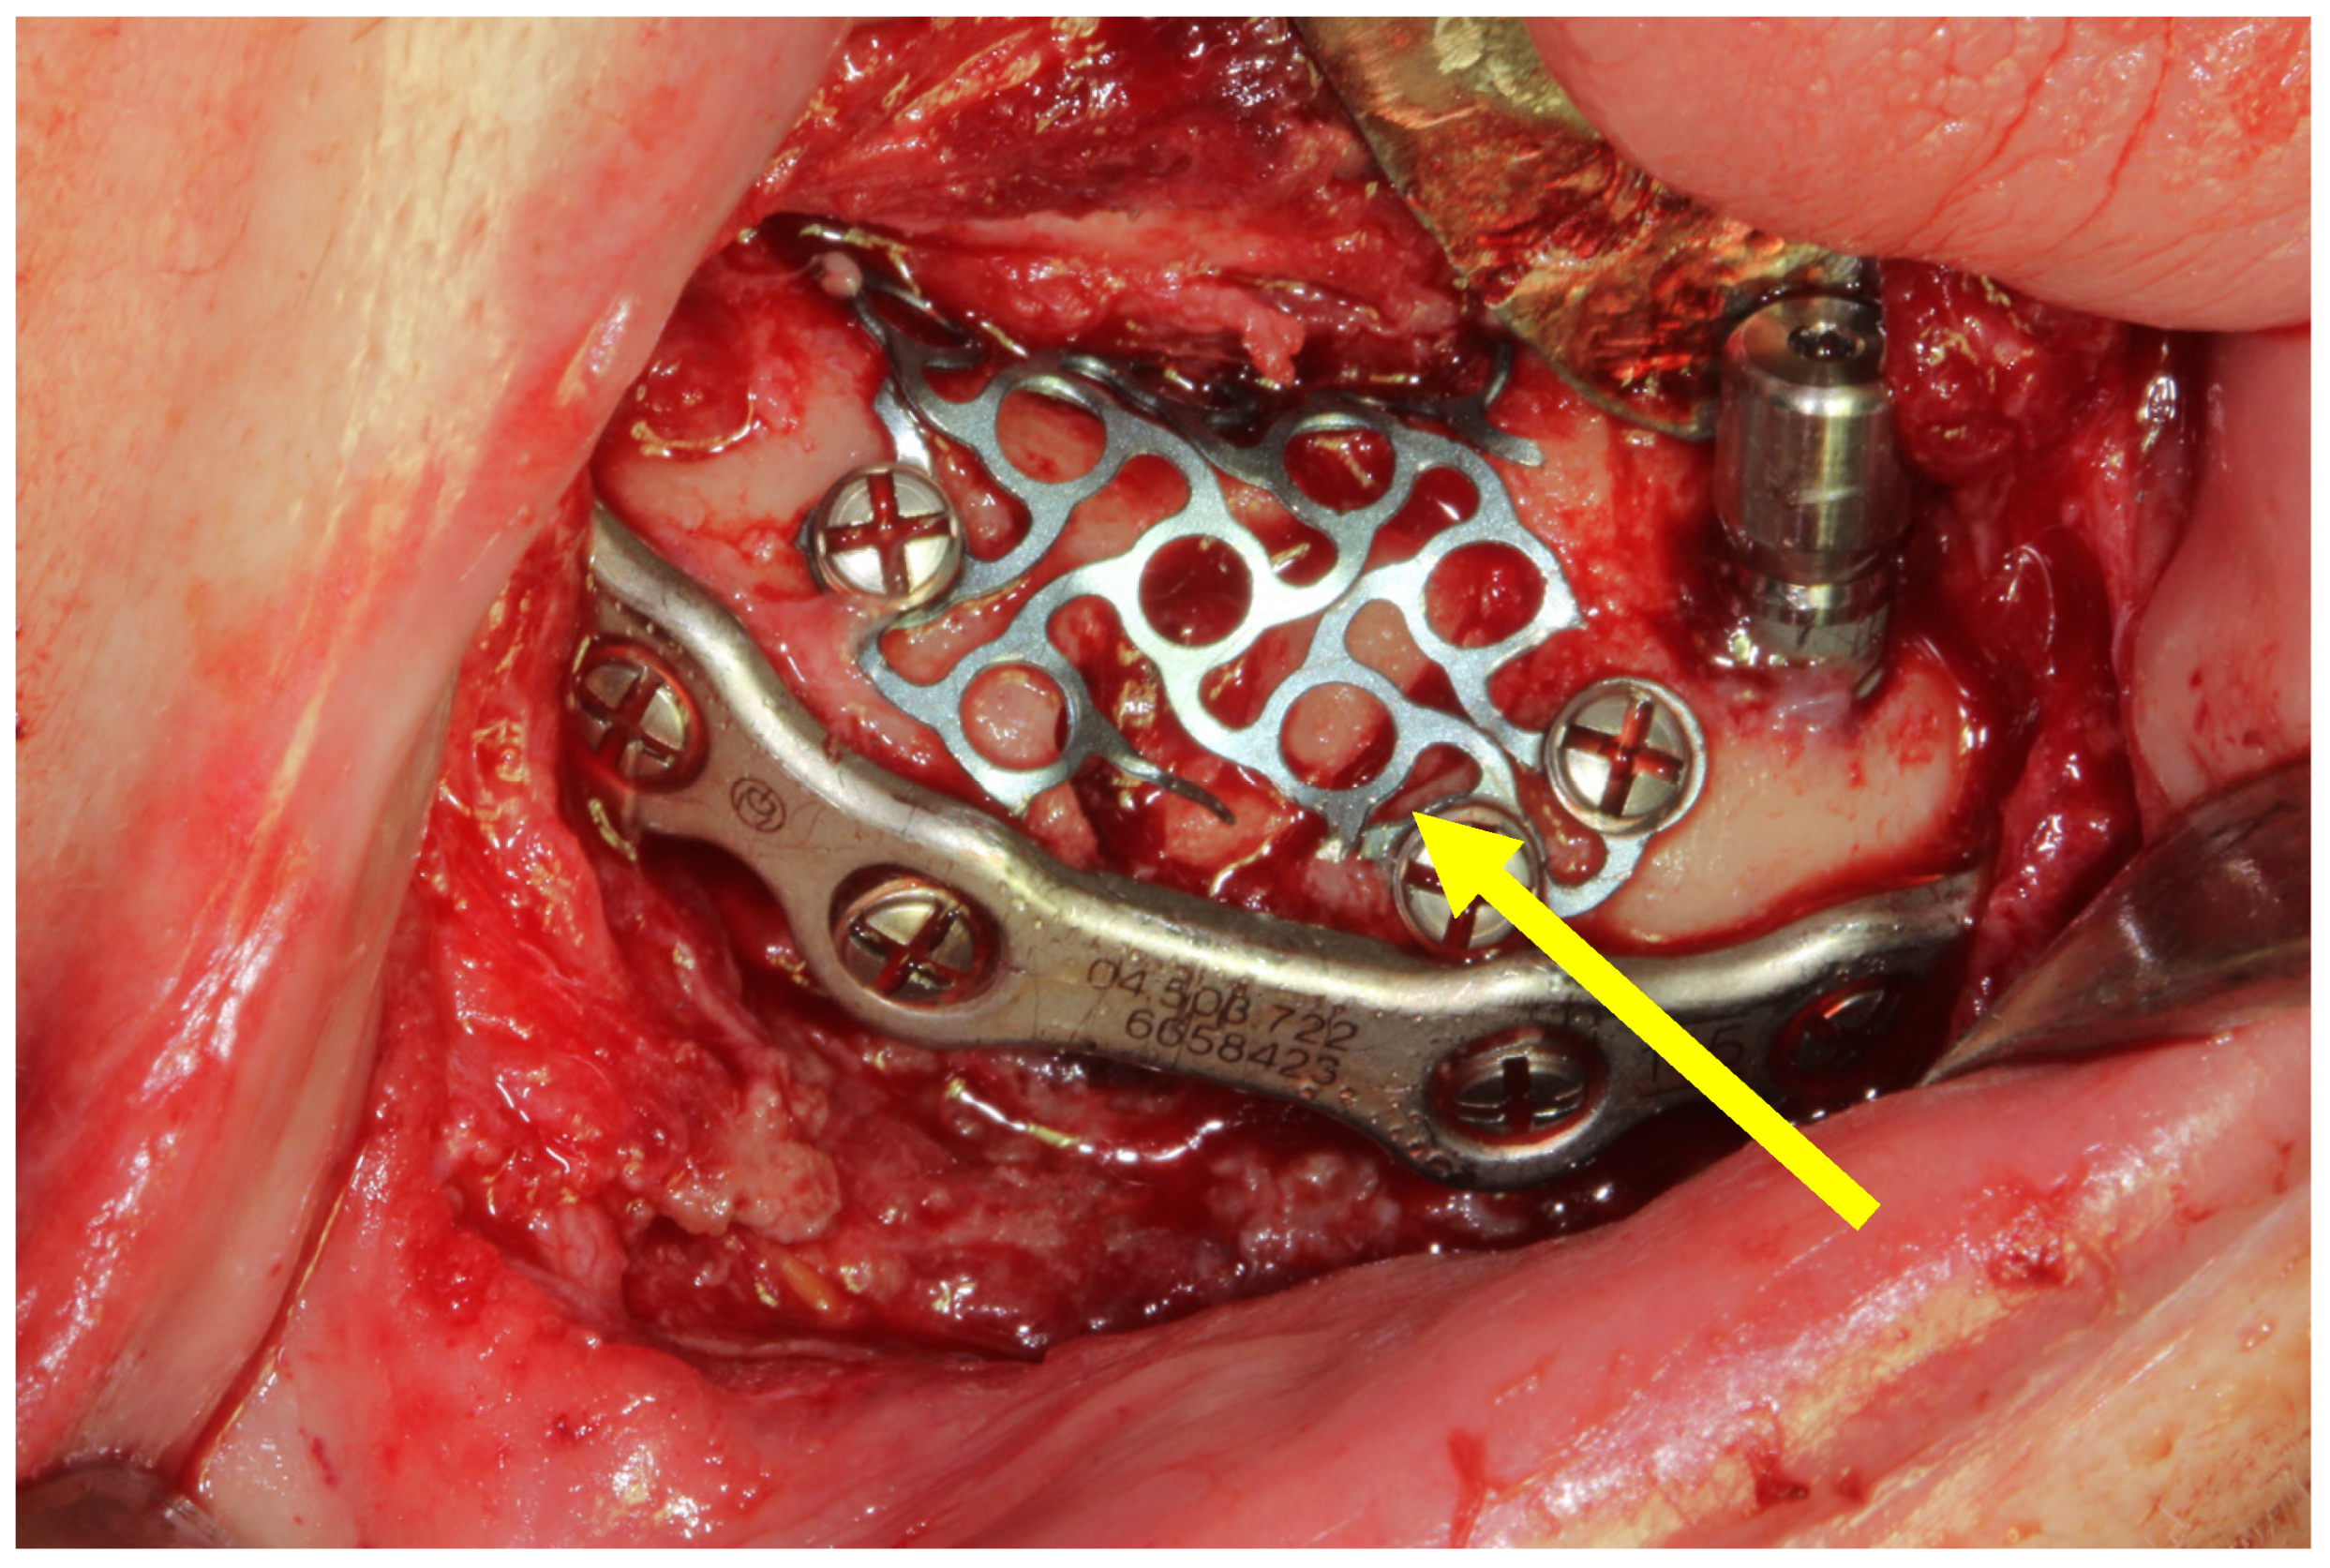

3.1. Case 1

3.2. Case 2

| Type of internal fixation | 2.5 mm thick mandibular locking plate with 2.4 mm screw diameter | 3 (50%) |

| 2.0 mm thick mandibular locking plate with 2 mm screw diameter + 1.0 mm thick mandibular plate with 2 mm screw diameter | 1 (16.67%) | |

| 2.0 mm thick mandibular locking plate with 2 mm screw diameter + titanium mesh | 1 (16.67%) | |